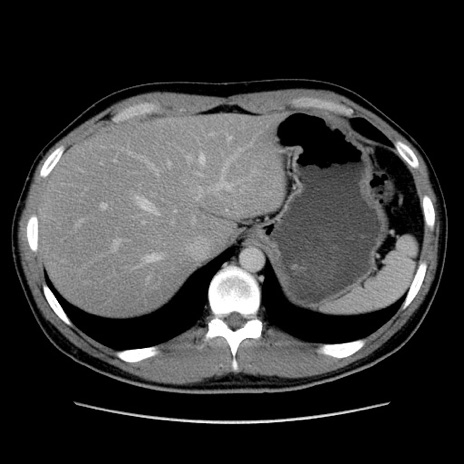

症例36(横断像)

【症例】20歳代 男性

【主訴】心窩部痛

【現病歴】今朝より上腹部痛あり。一旦軽快していたが再度出現したため救急要請。昨日夕に白身の魚を含む刺身を食べた。

【身体所見】BP 136/89mmHg、HR 74/min、BT 37.0℃、腹部:膨満、軟、心窩部に圧痛あり。反跳痛なし、筋性防御なし、腸雑音やや亢進あり。

【データ】WBC 17700、CRP 0.48